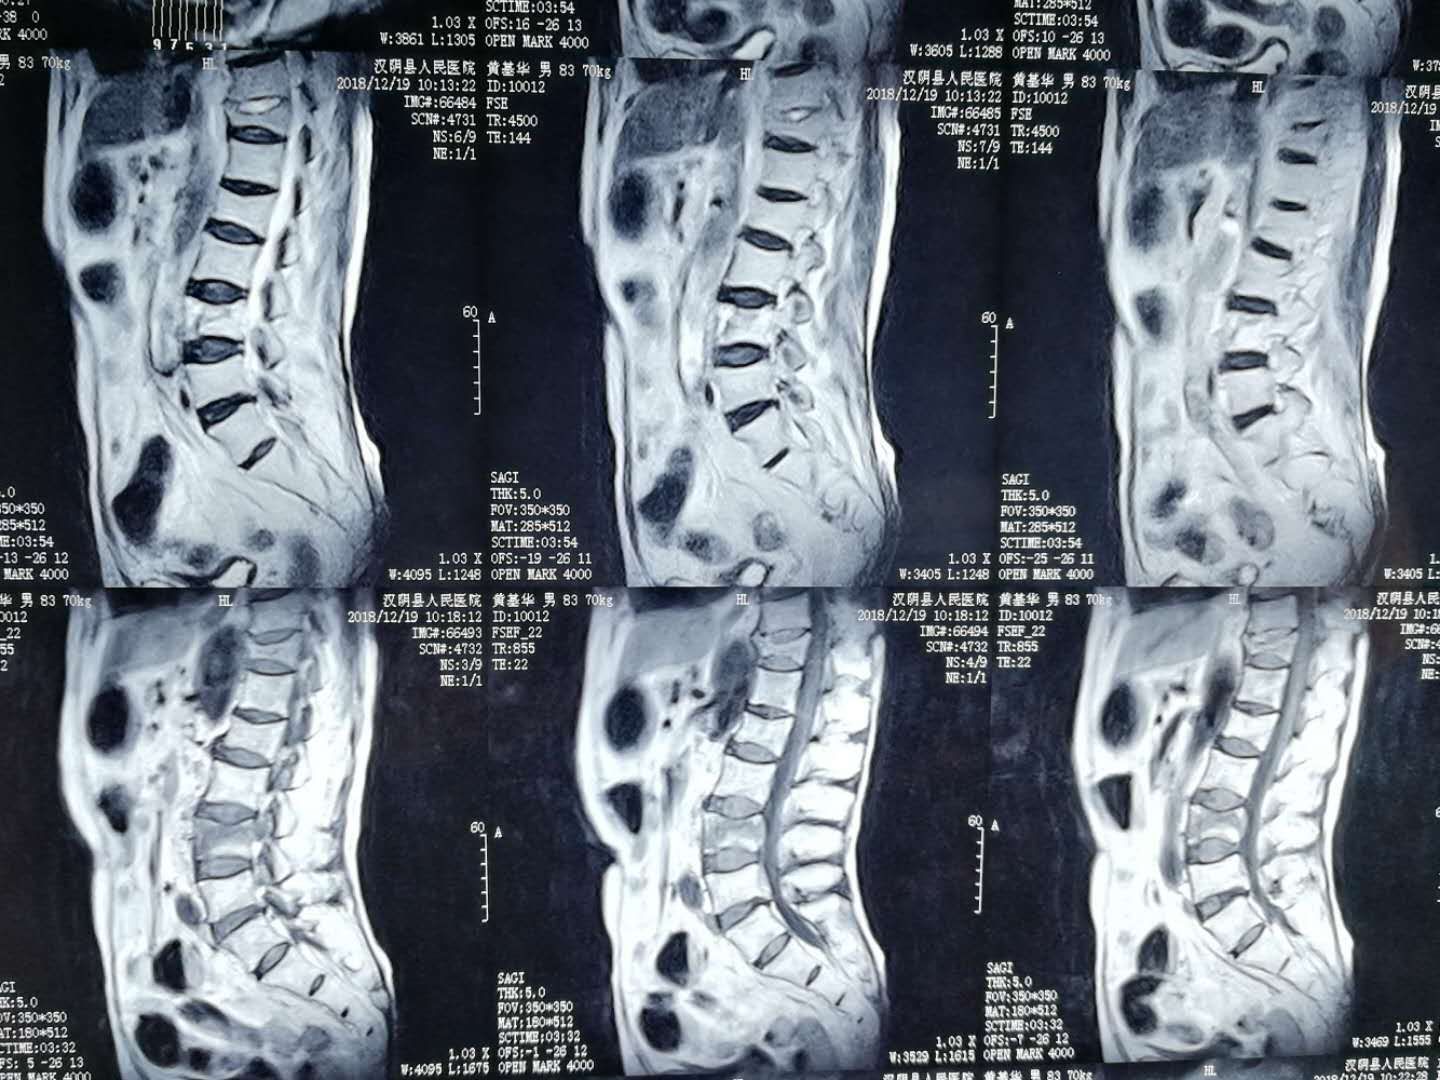

4月10日,黄阿姨在家人的搀扶下,来到该院外二科,经门诊医生查阅病史、查体后,以“腰4椎体压缩性骨折”之诊断收住入院。入院时黄阿姨腰部剧痛,活动受限,卧床翻身受限,站立及坐立困难,日常生活起居受影响,生活质量严重下降。黄阿姨被病痛折磨的苦不堪言,请求尽快手术治疗,力争早日开始正常生活。

急切想步入正常生活,这是医患之间的共同目标,但难题也同样摆在了该院外二科医师团队面前:患者高龄,切开复位手术风险较高,术后恢复较慢,且需行二次手术取出内固定,如果使用传统的手术方法,手术风险高且术后恢复较慢,且并发症较多,综合考虑后,决定行经皮椎体成形术。

椎体成形术,临床全称为经皮穿刺椎体成形术(percutaneous vertebro plasty,PVP),属于微创手术,是通过向病变椎体内注入骨水泥(聚丙烯酸甲酯,polymethylacrylate,PMMA)或人工骨达到强化椎体的技术。

做好各项术前检查后, 4月11日,在局部麻醉下行腰4椎体压缩骨折经皮椎体成形术,经过1个小时的精心手术,术后回到病房,黄阿姨诉腰部疼痛明显减轻,卧床翻身自如。